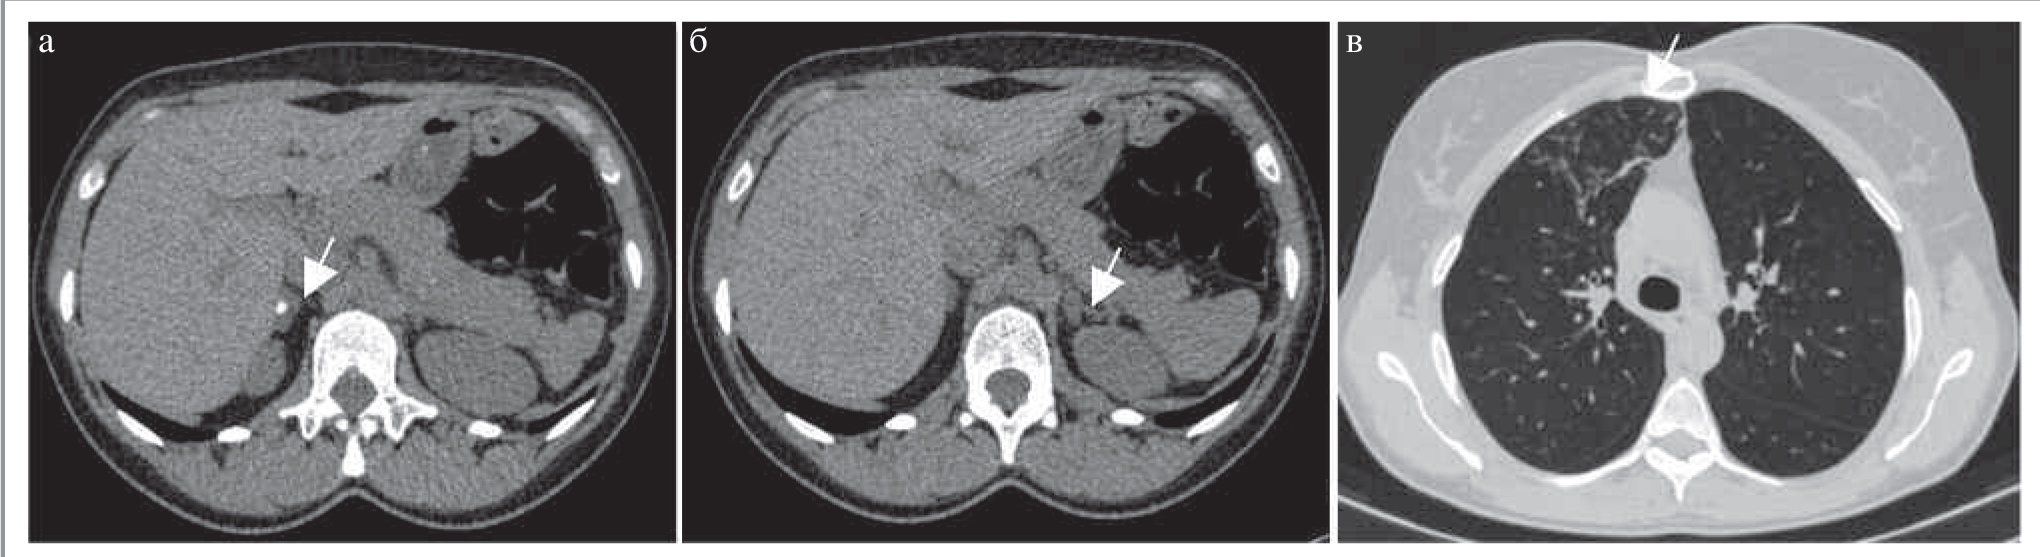

Нейробластомы представляют собой крупные образования неоднородной структуры, чаще поражающие надпочечники, но так же, как и феохромоцитомы, могут быть обнаружены в любом другом месте вдоль симпатического ствола [12]. КТ-картина сходна с АКР и лимфомой (рис. 10). Для нейробластомы характерен выраженный инвазивный рост. Наиболее часто метастазы этой опухоли обнаруживают в печени и костях. Основным заболеванием, с которым следует дифференцировать нейробластому, является нефробластома (опухоль Вильмса). Для нейробластомы характерны наличие кальцинатов, охватывание сосудов без их инвазии, возраст пациентов до 2 лет, нечеткие, неровные контуры и распространение образования в контрлатеральную сторону за пределы срединной линии. Опухоль Вильмса, наоборот, характерна для детей более старшего возраста (3–4 года), имеет более четкие, ровные контуры. Для нее характерны смещение и инвазия сосудов (например, нижней полой вены).

Рис. 10. МСКТ, аксиальная проекция. Нейробластома левого надпочечника. КТ-изображения в аксиальной проекции: а – НФ; б – АФ; в – ВФ. В левом надпочечнике определяется неправильной формы образование с зонами обызвествлений (длинная стрелка) и участками некроза (короткая стрелка). Солидный компонент (звезда) умеренно накапливает контрастный препарат. (Изображения представлены с любезного разрешения д.м.н., проф. А.В. Горбунова и Д.Г. Коваленко, ГБУЗ «Морозовская детская городская клиническая больница» Департамента здравоохранения г. Москвы.)